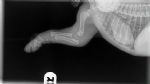

When you get your 8/10 week old puppies, please keep this image in mind. Although this photo is a very young puppy, it's to show how much has yet to be formed.  Their bones do not even touch yet. They plod around so cutely with big floppy paws and wobbly movement because their joints are entirely made up of muscle, tendons, ligaments with skin covering. Nothing is fitting tightly together or has a true socket yet.

A bit of back-story: This is a baby puppy who had a knock to his elbow and wasn't using it properly, so he was taken to the vet. There is nothing wrong in these x-rays, thankfully it is a soft tissue injury and he is expected to be fine.